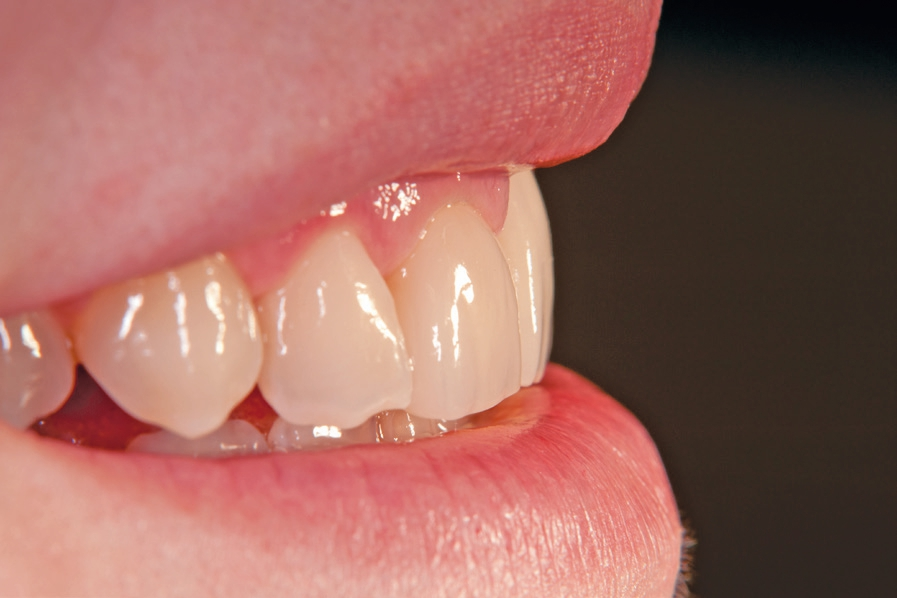

Gleichzeitig mit der prothetischen Versorgung des Implantats wurde auch für Zahn 11 ein Veneer geplant. Zum Einsatz kam ein Zeramex T Implantat Durchmesser 5,5 mm, Länge 12 mm. Für die Kronenversorgung wurde ein mit e. Max überpresstes CAD-Abutment gewählt. Während der Einheilphase des Implantats kam eine Sunflex-Prothese zum Einsatz.